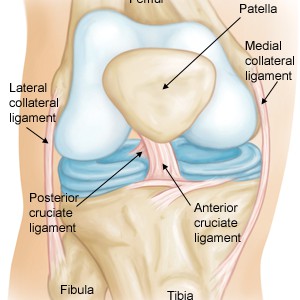

Diz eklemi; uyluk kemiği...

Ön-Arka Çapraz Bağ Yırtıkları

&nbs...